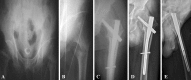

Methods: We conducted a pilot prospective randomized controlled trial comparing standard versus long (≥ 34 cm) intramedullary hip nails for reverse obliquity fractures of the proximal femur from January 2009 to December 2009. There were 15 patients with standard nails and 18 with long nails. Mean age was 79 years (range, 67-95 years). We determined 1-year mortality rates, reoperation rates, Parker-Palmer mobility and Harris hip scores, and radiographic findings (fracture union, blade cut-out, tip-apex distance, implant failure). Minimum followup was 12 months (mean, 14 months; range, 12-20 months).

Results: We found no difference in reoperation rates between groups. Two patients (both from the long-nail group) underwent revision surgery because of implant failure in one and deep infection in the other. There was no difference between the standard- and long-nail groups in mortality rate (17% versus 18%), Parker-Palmer mobility score (five versus six), Harris hip score (74 versus 79), union rate (100% in both groups), blade cut-out (zero versus one), and tip-apex distance (22 versus 24 mm).

Conclusions: Our preliminary data suggest reverse obliquity fractures of the trochanteric region of the femur can be treated with either standard or long intramedullary nails.